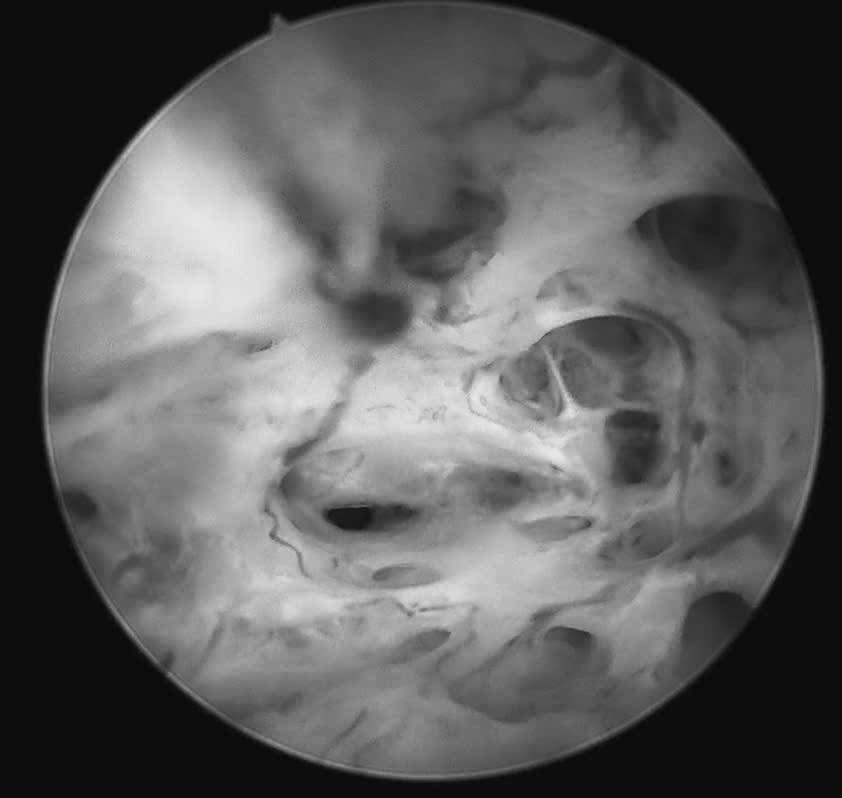

Rong kinh kéo dài nhưng việc thăm dò chẩn đoán bị trì hoãn do lo ngại giữ "cái ngàn vàng", nữ bệnh nhân 30 tuổi được phát hiện ung thư niêm mạc tử cung sau khi thực hiện soi buồng tử cung sinh thiết. Câu chuyện đặt ra cảnh báo về những rào cản tâm lý có thể khiến người bệnh đánh mất cơ hội điều trị sớm.